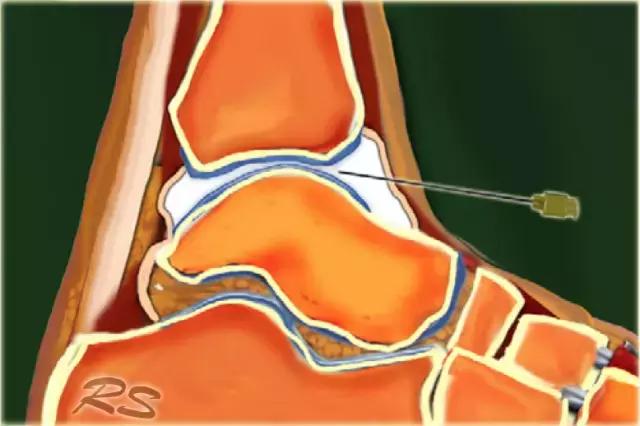

胫骨关节 CT或MR关节镜可用于查询韧带,骨软骨或软骨损伤,评价自由体或查询骨软骨病变的稳定性。对于踝关节(胫骨关节)的注射,患者仰卧,足部轻微的跖屈。用超声波检查胫骨关节的内侧,以确定合适的注射部位,同时检查任何过量的关节液。我们使用小型弯曲阵列8 MHz传感器,但如果优选,可以使用18-12 MHz线性阵列传感器。 探头的长轴保持在矢状面内。

通常为22号(长度:30mm)的针被引入与在前关节空间的内侧上的换能器的长成像轴线,内侧到前胫骨韧带,避免韧带和血管。应该确定距骨穹顶和悬垂的前胫骨唇。 针头在胫骨远端成角度地进入远侧胫骨的腹侧唇下的关节,瞄准远侧胫骨的关节表面。感觉到接触,并且再次确保针尖离开胫骨软骨并且斜面面向接头。

将8-10ml的对比剂注入胫骨关节,并且看到前囊与流体一起膨胀。

患者不应该有疼痛而抵抗。